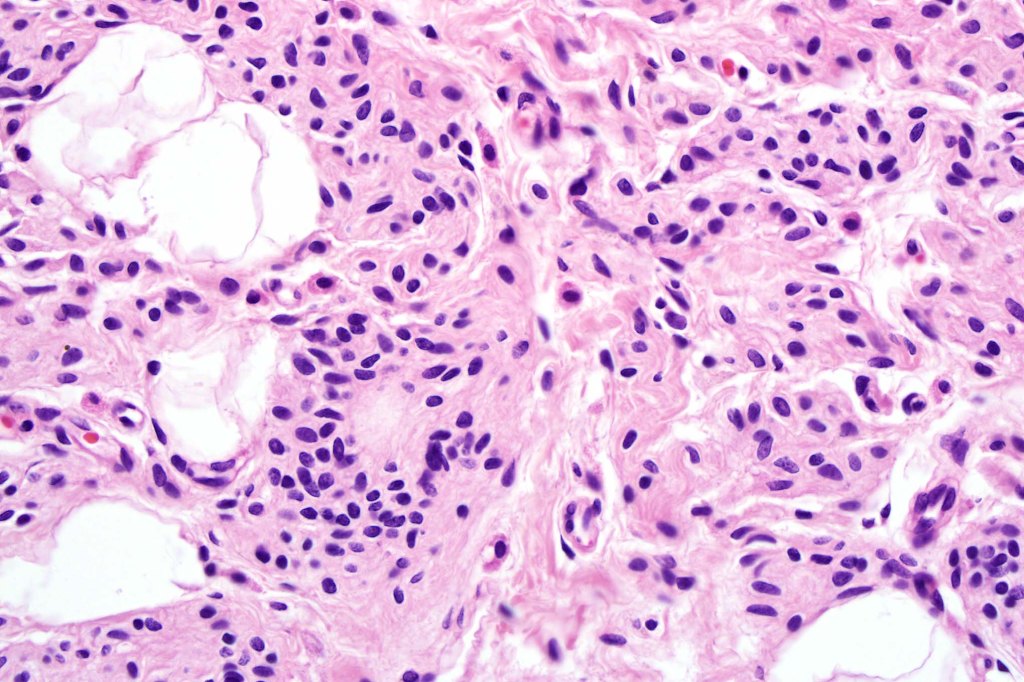

•It is hypercellular and most often composed of epithelioid cells showing little pleomorphism & only occasional mitoses

•Nuleoli are small

•Intracytoplasmic pseudo-inclusions

•The constituent cells are generally larger than the adjacent nevus cells

•Some examples show more marked pleomorphism with prominent nucleoli and increased mitotic activity but abnormal mitoses are not a feature. These are not associated with any sinister biological potential